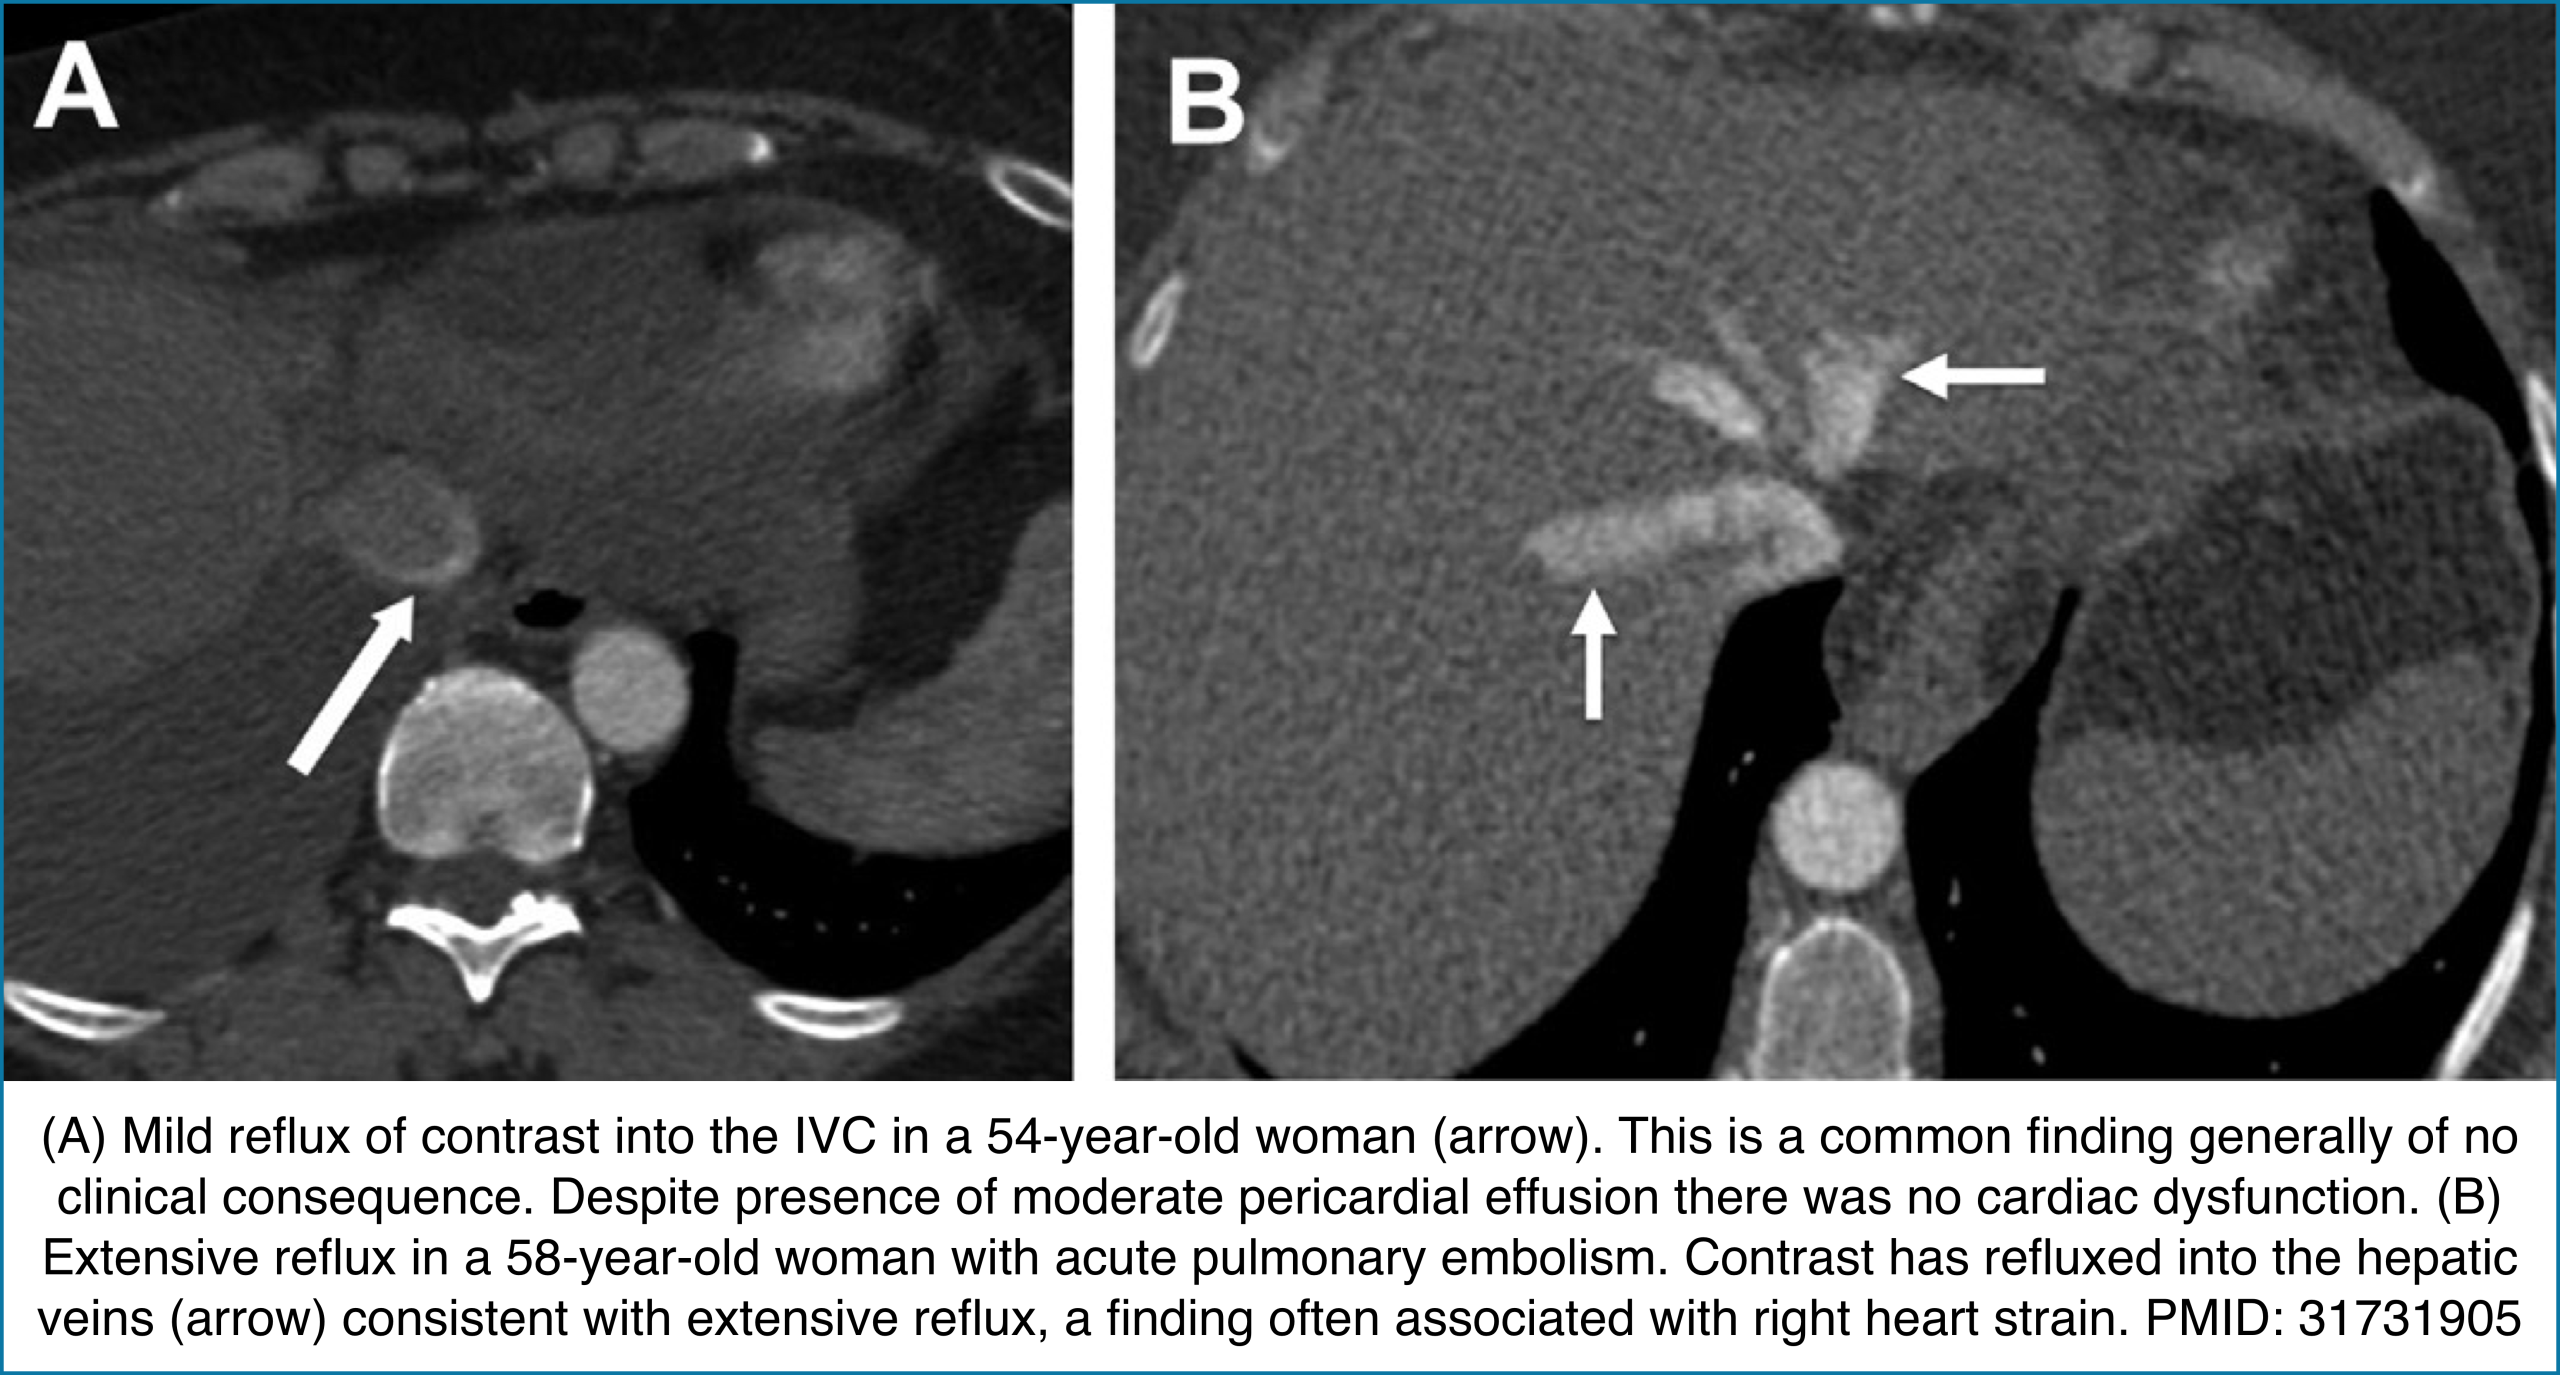

◾️Contrast reflux into the inferior vena cava and hepatic veins

- Reflux of contrast from the right atrium into the IVC can indicate impaired right ventricular forward flow. While it may occur with PE, tricuspid regurgitation, or pericardial disease, its diagnostic value is heavily influenced by injection technique.

- Key Pearls

- Contrast reflux → Suggests RV failure from causes such as PE, TR, or pericardial pathology.

- Diagnostic performance varies with injection rate:

- <3 mL/s (routine CT): ~31% sensitivity, ~98% specificity.

- >3 mL/s (CTA): ~81% sensitivity, ~69% specificity.